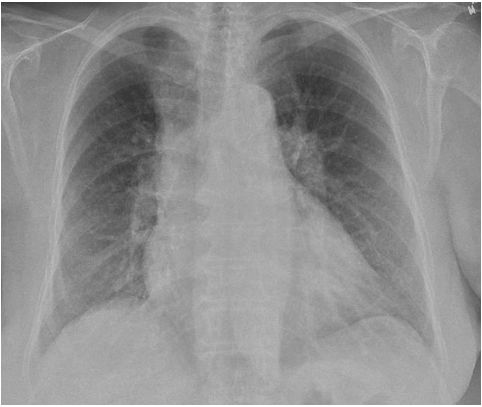

心电图可能表现为急性下壁梗死或下壁导联Q波,提示陈旧性下壁心肌梗死。电轴右偏、右束支传导阻滞或V1导联高耸R波(高于相应的S波)均为右心室疾病的可能表现。胸部透视可见增大的右心房或右心室(图20-2),而肺部征象随病因不同变化很大。

图20-2 原发性肺动脉高压患者增大的右心房、右心室以及双侧肺动脉